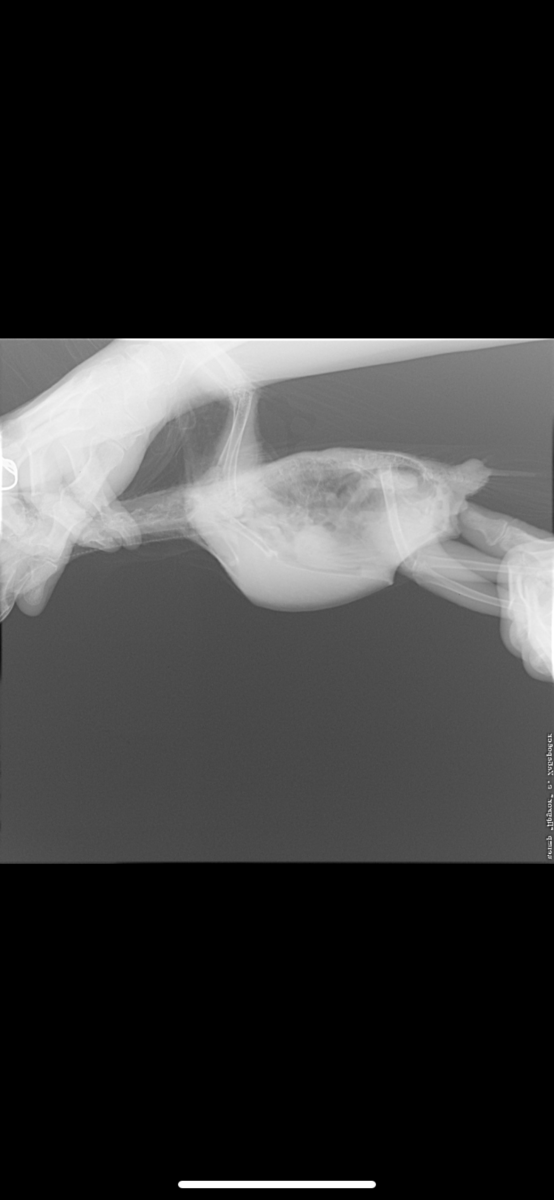

Koalla88 Опубликовано 26 февраля, 2020 #9 Опубликовано 26 февраля, 2020 @Жора жако гепатовет для кошек дают попугаям, это очень не плохой гепапротектор. Жако лечат вифендом, т.к. они этот препарат более-менее нормально переносят. Боятся выдержит ли птиц не стоит, тут два варианта - либо лечитесь и смотрите на динамику, либо просто наблюдайте, как птиц медленно умирает. Не будете лечить, птица однозначно погибнет. Поэтому пробуйте, в случае чего потом себя вам хотя бы будет не в чем упрекнуть.

Zosia Опубликовано 2 марта, 2020 #42 Опубликовано 2 марта, 2020 Обсудите с вашим врачом ингаляционное применение Энилконазола (торговые наименования и формы м.б. разные). Это- параллельно с вориконазолом. И нет ли у птицы "синдрома исчезающего легкого"... какой-то мне рентген привиделся...тревожный.

Жора жако Опубликовано 7 марта, 2020 Автор #43 Опубликовано 7 марта, 2020 03.03.2020 в 07:57, Zosia сказал: Обсудите с вашим врачом ингаляционное применение Энилконазола (торговые наименования и формы м.б. разные). Это- параллельно с вориконазолом. И нет ли у птицы "синдрома исчезающего легкого"... какой-то мне рентген привиделся...тревожный. Здравствуйте) Не увидели такого синдрома, симптомов никто из орнитологов не нашли Про энилконазол мне ответили, что Жако такого не назначают, так как не переносимость его???? Мы сдали биохимию и результаты не утешительны, к сожалению, особенно, что касается печени( боюсь, что может не выдержать лечение. @Zosia как специалист по Жако и по лечением травами, прошу вас посоветовать нашему птенцу ещё какую-нибудь поддержку, кроме гептрала ? (принимаем 1 таблетку в сутки, разделенную на 2 приема) Жорушка всё также не активный, сама его кормлю, так как не хочет есть (максимум подходит 1 раз к кормушке и 3-5 семечек может съесть), грудная клетка всё также увеличивается при дыхании, как на видео выше, практически не летает, ощипал себе шею, так как из-за постоянных кормлений, не всегда оперение супер чистое (стараюсь мыть после каждого кормления/дачи препаратов), контролируем анализ кала на наличие дрожжей, их нет. Из назначений: принимаем ворикоз , сумамед, гептрал, также с понедельника будут инъекции кальция внутримышечно ежедневно.